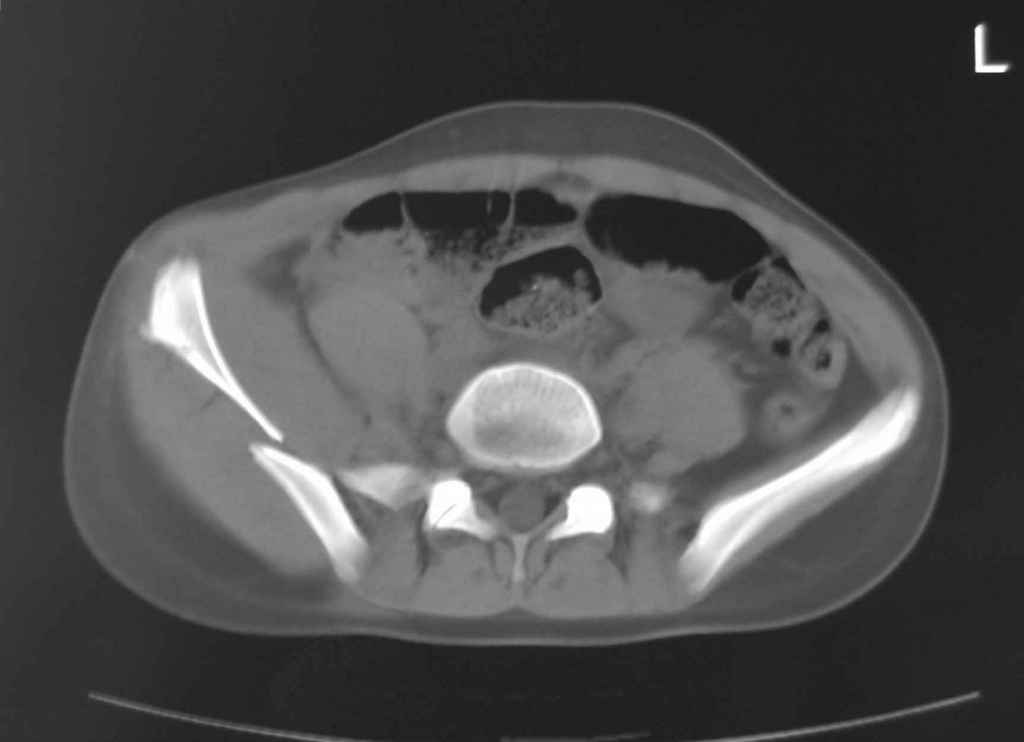

Принципиально важно видеть все срезы КТ через вертлугу, так как тактика лечения будет в первую очередь обусловлена характером перелома ветрлужной впадины, во вторую - вертикальным смещением таза ( где варианты - от банального скелетного вытяжения до ВЧКО или накостного остеосинтеза - в основном зависит от пресловутой "позиции кафедры")

Уважаемый Алексей, на представленных Вами снимках имеется вертикально-нестабильное повреждение тазового кольца без повреждения вертлужной впадины. Учитывая это, а так же растущий возраст ребенка я бы выбрал аппарат внешней фиксации в виде кольцевой опоры, т.к. не смотря на оскольчатый перелом крыла в переднем отделе можно ввести минимум 2 стержня + 1-2 надвертлужно. Этого будет достаточно чтобы "зацепится", выполнить репозицию и дальнейшую фиксацию. Перелом шейки по моему лучше прооперировать 3 канюлированными винтами по АО.